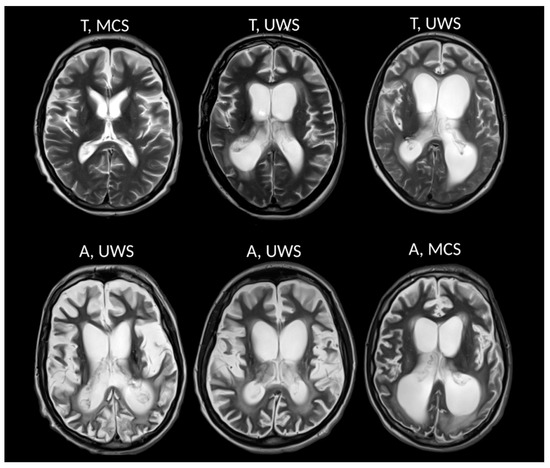

3.2. Anoxia versus Trauma Patient Groups

3.3. VS/UWS versus MCS Patients Groups